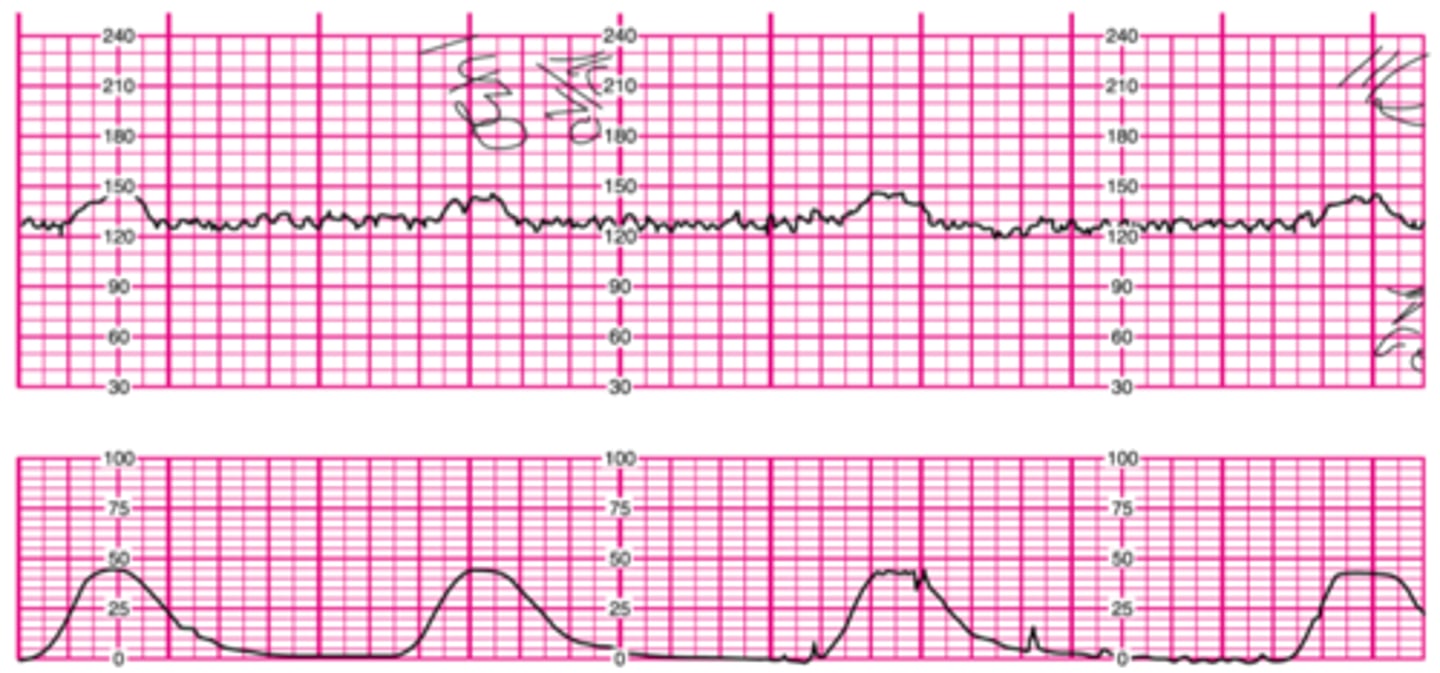

Late decelerations

- occur with contractions, fetal baseline is not back up after the contraction is over

- NOT GOOD

-immediately call to provider, letting them know what you are seeing, and what you have done

What do you do when there is late decelerations?

- immediately change position

- apply oxygen

- if mom is getting pitocin, slow down or cut it off

- IV fluids

- get ready for a quick delivery or c-section